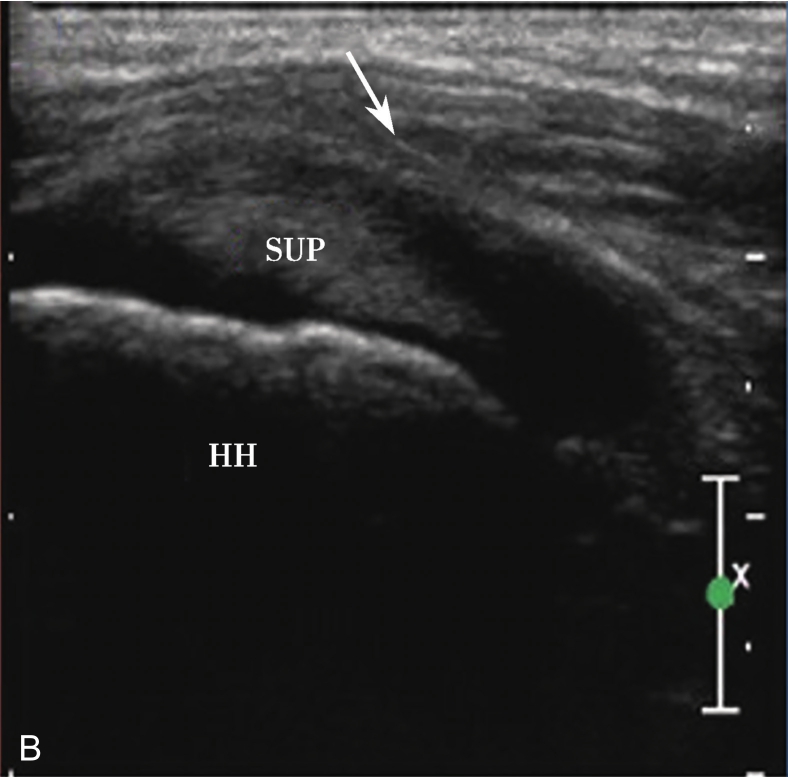

3.当肩袖回声不均匀,有可疑的滑囊面撕裂或全层撕裂,行超声引导下肩峰下-三角肌下滑囊造影检查,可提高对肩袖撕裂的诊断率。方法:将2~5ml生理盐水与0.5ml的超声造影剂混合后,注入肩峰下-三角肌下滑囊,无撕裂的滑囊呈线状高增强(图2-1-8),肩袖滑囊面部分撕裂可见造影剂混合液从滑囊进入肩袖肌腱内而未达肱骨头表面(图2-1-9),若观察到其进入肩关节腔或肱二头肌长头腱鞘,则诊断肩袖全层撕裂(图2-1-10)。

▲ 图2-1-9 超声引导下肩峰下-三角肌下滑囊造影图(二)

A.超声引导下滑囊内注入超声造影剂后,滑囊呈线状高增强,肌腱内可见局限性高增强,提示肌腱滑囊面部分撕裂(箭头);B.二维超声显示冈上肌腱(SUP)回声不均匀(箭头),但未见明显撕裂,HH:肱骨头